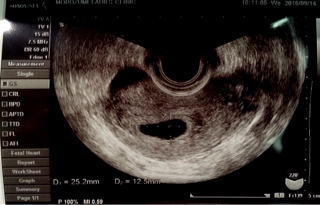

テーマ:不妊治療 BT32/D50(7w3d) ついに運命の日がやってきました…。 今日、心拍が確認できなければ、 その先は決まっています。 昨夜は緊張して寝付けず、 夜中にも起きてしまうほどでした…。 今日は1日有給休暇を取り、診察へ。 昨夜はプロジェクトの初飲み会だったため、なんとか参加しましたが、 やはり体調はあまり良くありません。 咽喉元ムカムカは変わらずだし、 めまいや頭痛もします。 ただ、座って何かを口に入れている事の方がまだ楽でした。 ◆9:50受付(10:...